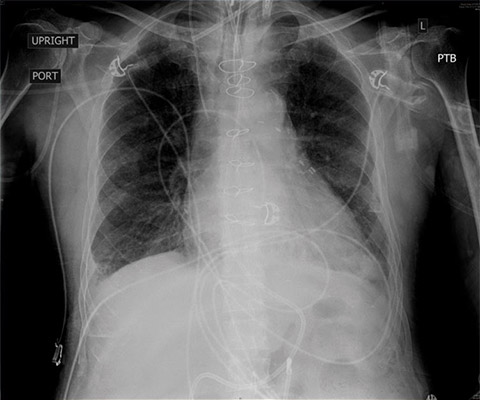

Given his renal failure and anticipated limitations to aggressive diuresis with medical therapy, arrangements were made to emergently intubate the patient, augment ionotropic support, escalate diuresis attempts with diuretics while calling the family to discuss care options including likely need for dialysis. As the patient was being prepped for intubation, X-ray imaging was obtained confirming the diagnosis of pulmonary edema. By then, though, the patient had already been given aggressive diuretic therapy, received escalating ionotropic support, bronchoscopy was set up at the bedside for endobronchial evaluation after the intubation given his fevers, and the family had been notified. POCUS with a small, extremely portable device had allowed for convenient and rapid evaluation, diagnosis, and intervention in a complex patient. A repeat chest X-ray just one hour after intubation showed marked improvement in the patient’s pulmonary edema.Clinical impact

CXR one-hour status post intubation, after initiation of aggressive diuresis, augmentation of ionotropic support, and positive pressure ventilation.